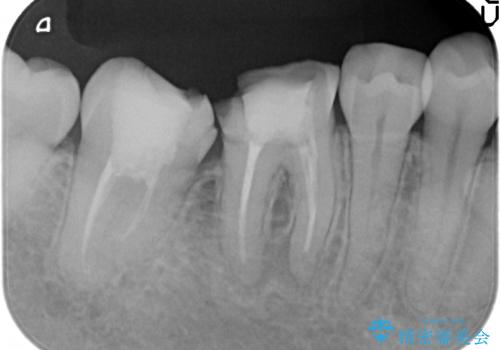

- 奥歯が欠けてしまったので診て欲しいといらっしゃった方の症例です。

再根管治療終了後、オールセラミッククラウンによる補綴を行いました。

今回用いたオールセラミッククラウンはジルコニアフレームという白い素材の上にセラミックを盛っているため、審美性が非常に高いのが特徴です。

また、ジルコニアは人工ダイヤモンドの材料にも使われているほど高い強度を持っており、そのためオールセラミッククラウンは審美性だけでなく、奥歯やブリッジの補綴も可能とするクラウンです。